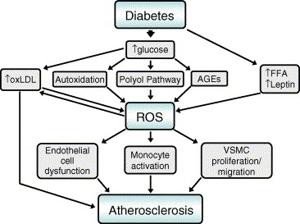

DFUs are open wounds or ulcers that usually develop on the lower part of the foot in diabetic patients. They ocurr due to diabetes complications like peripheral neuropathy (nerve damage), lack of circulation (ischemia), and infection. These ulcers are severe as they raise the susceptibility of infections. It may result in hospitalization, amputation and severe health complication without treatment.

Revascularization

· Wound healing potential may require interventions to enhance the circulation with vascular surgery or angioplasty as in the case of patients with poor blood flow.

· Poor glycemic control, infection severity, ischemia, and neuropathy aggravate prognosis.